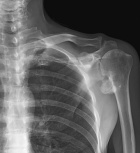

48 year old AAM with a two month history of a painful right shoulder and inability to reach overhead

Zoom image: Radiological image Radiological image.